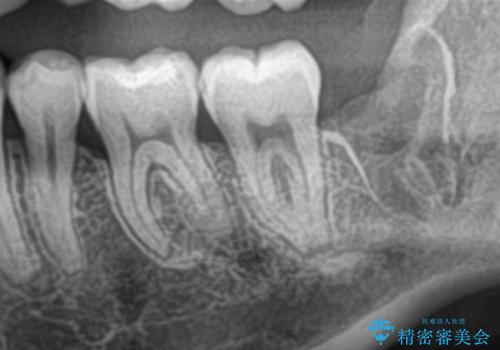

- 親知らずを抜きたいとのことで来院された患者様です。

CTで神経の位置などを確認し、抜歯術を行いました。